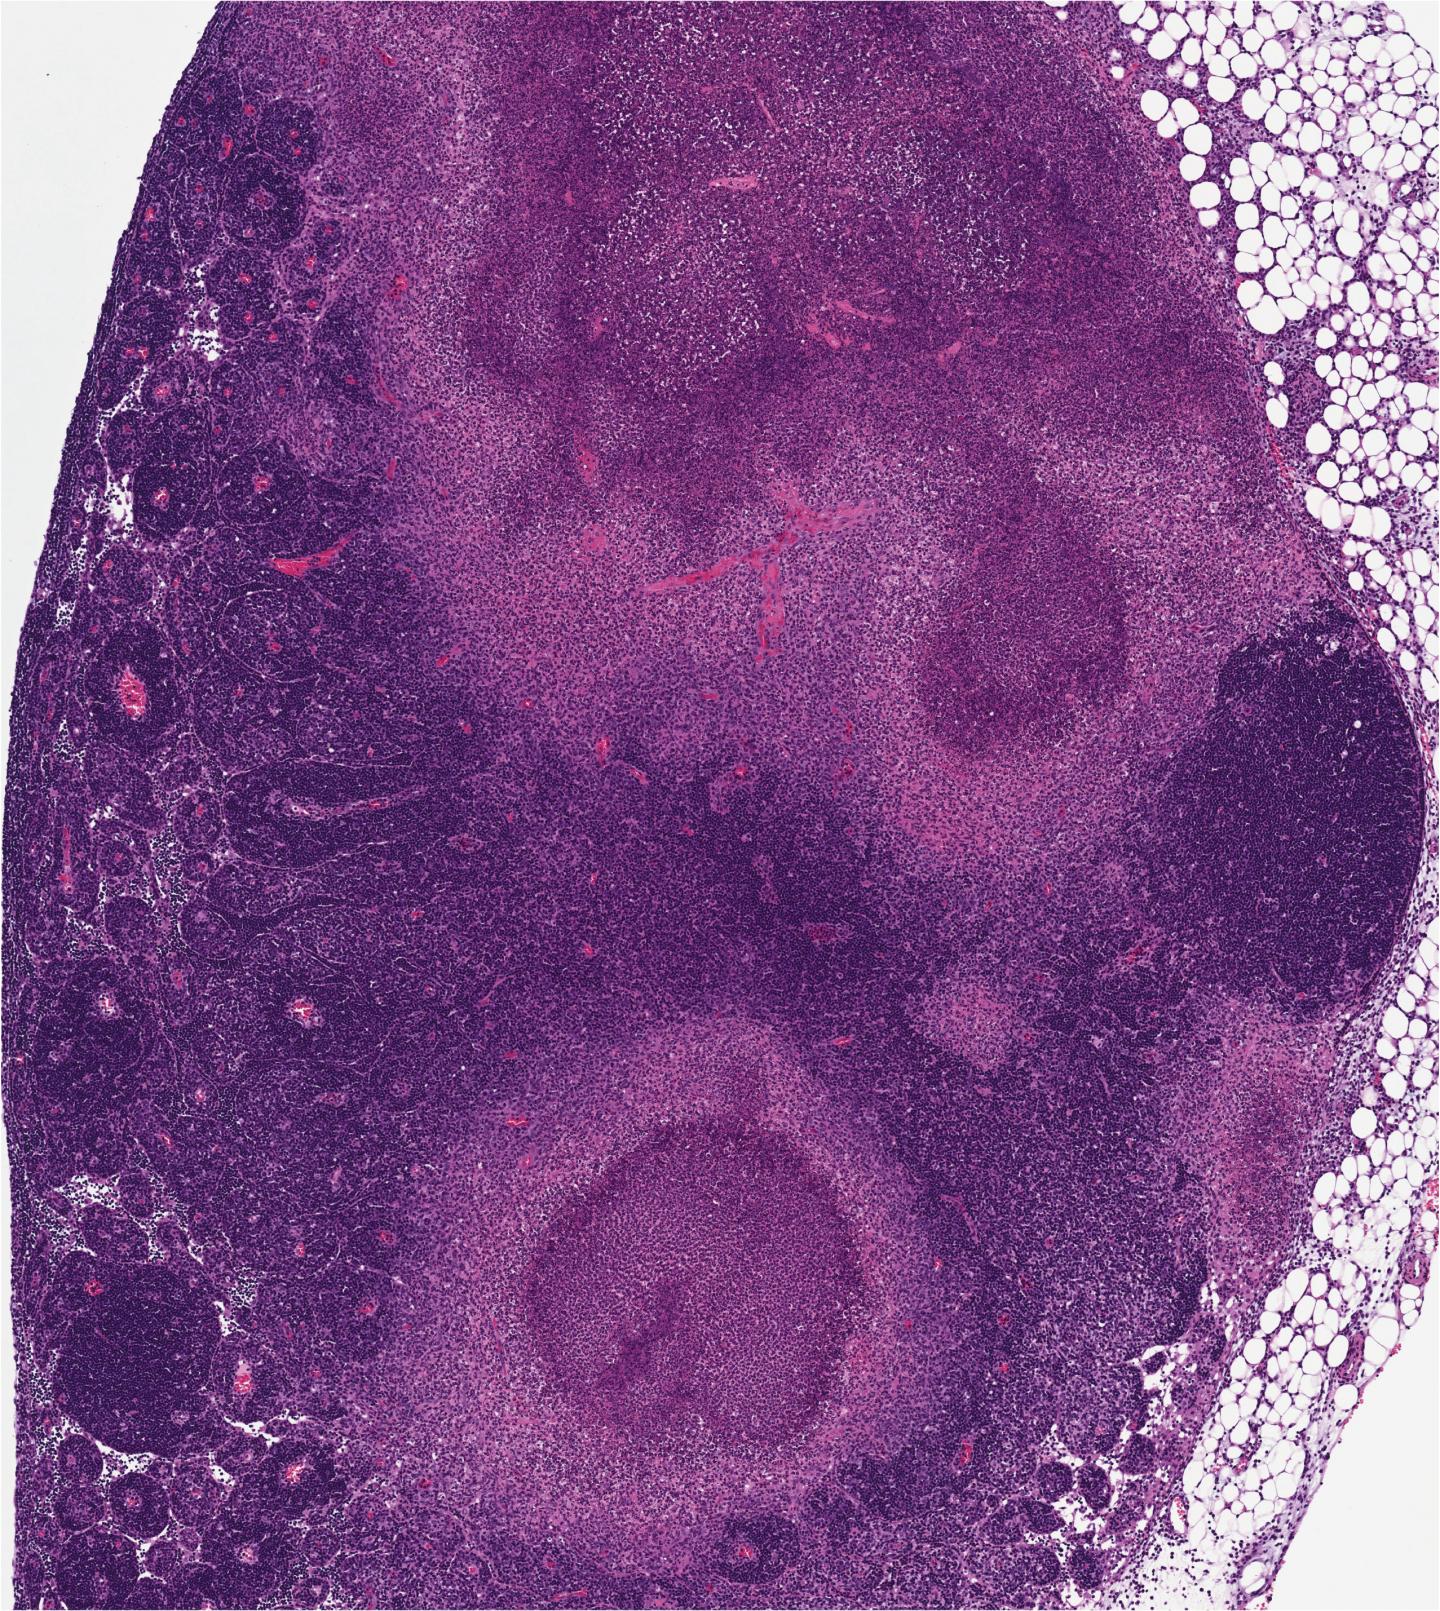

The researchers also noticed that the infected lymph nodes from mice that could not undergo RIPK1-induced apoptosis were unable to form granulomas, areas of organized immune cells that can form in response to many infectious or inflammatory stimuli, and are thought to be places of bacterial containment. This suggested that RIPK1-induced apoptosis might promote containment of the bacteria by allowing the immune system to form these granulomas.